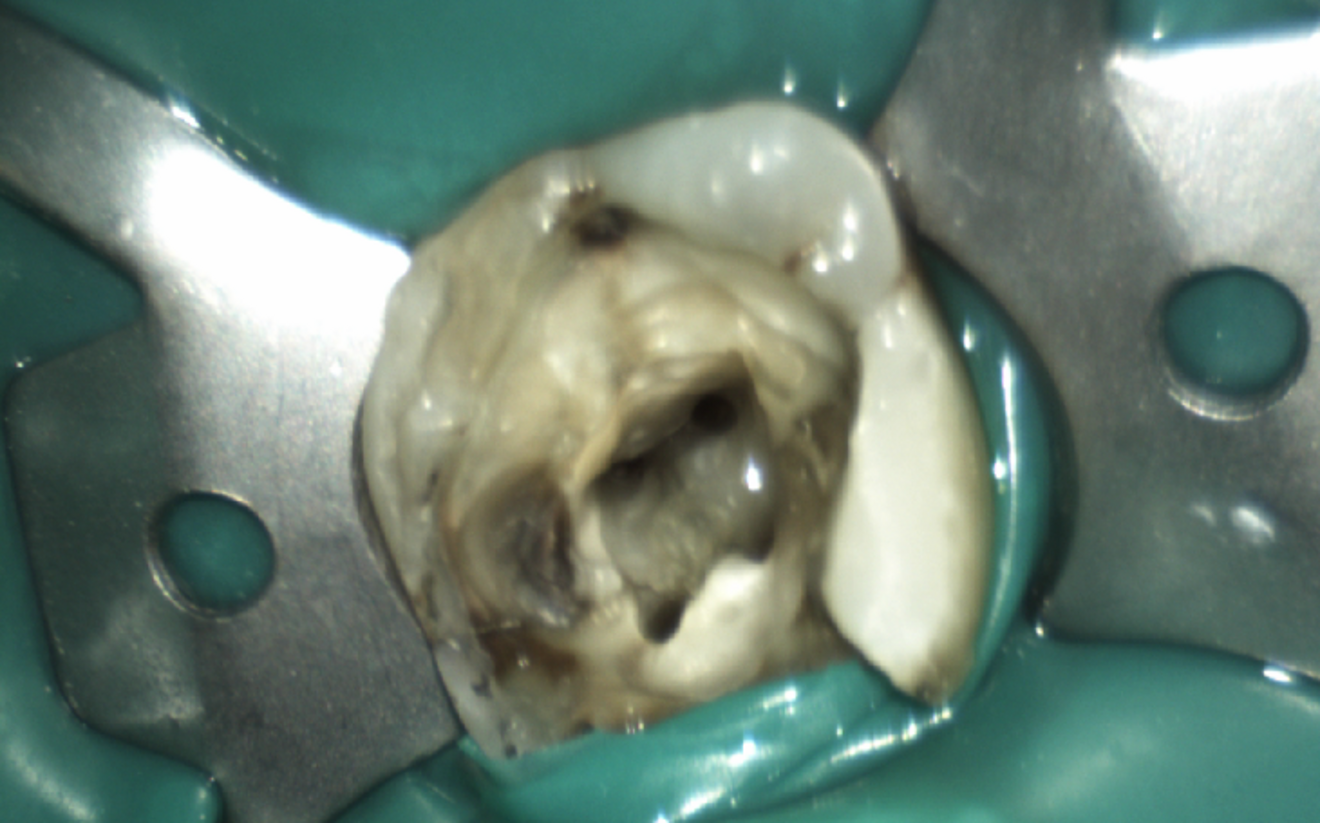

Fig. 2: Access to the pulp chamber showing four canals.

A total of four canals were identified (Fig. 2). The treatment started with continuous delivery of sodium hypochlorite (NaClO) solution (3 ml) by syringe and simultaneous activation by Er:YAG laser. Laser-assisted irrigation was performed with a LightWalker AT-S (Fotona) and an Er:YAG H14 handpiece with a flat SWEEPS 400/9 fibre tip positioned safely at the entrance to the pulp orifice (Table 1). For the shaping of the root canal system, the ProTaper Gold rotary file system (Dentsply Sirona) was used. Minimally invasive root canal preparation began with the 19/0.04 SX file to relocate the coronal aspect of the canals. Cleaning and shaping of the canals were subsequently performed with the 18/0.02 S1 file and 20/0.07 F1 file to the working length.